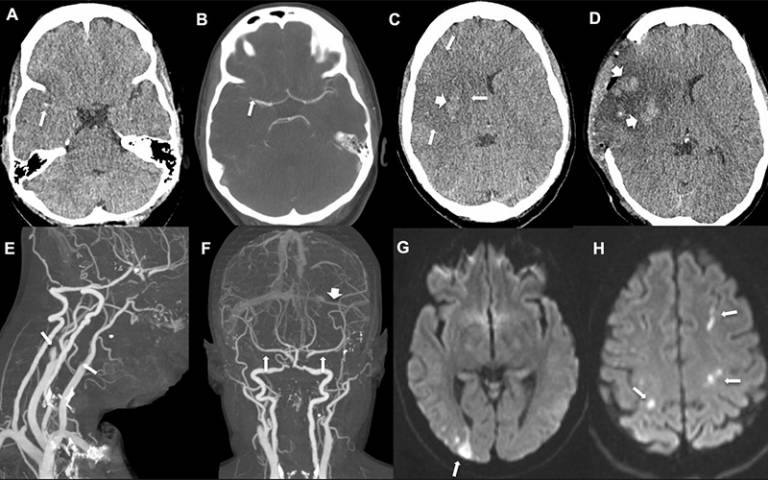

Kot ugotavlja Emin Odbor za varnost zdravil (PRAC), so se pri VITT krvni strdki pojavili v venah v možganih in trebuhu ter v arterijah. VITT se pojavi od štiri do 28 dni po cepljenju, največkrat v dveh tednih po prvem odmerku. Glede drugega odmerka je zaradi majhnega števila cepljenih za zdaj še premalo podatkov.

V Sloveniji je bil doslej potrjen en primer trombotične trombocitopenije, ki je nastala kot posledica cepljenja s cepivom AstraZenece. 50-letno bolnico so uspešno pozdravili na nevrološki kliniki.

Med njimi je en primer, pri katerem so nastale nevrološke motnje (parestezije in izguba moči v okončinah) in trombocitopenije. Strokovnjaki so ocenili, da je v tem primeru povezava s cepljenjem možna.

Več primerov je še v fazi preiskave. Med tistimi, ki so zahtevali hospitalizacijo, so navedeni tudi po en primer venske tromboze, en primer pljučne embolije in en primer tromboze možganske arterije s trombocitopenijo in tromboze arterije.

V drugem primeru je šlo za možgansko kap, v tretjem pa za vensko trombozo. Tudi ta dva primera sta še v fazi zbiranja podatkov.